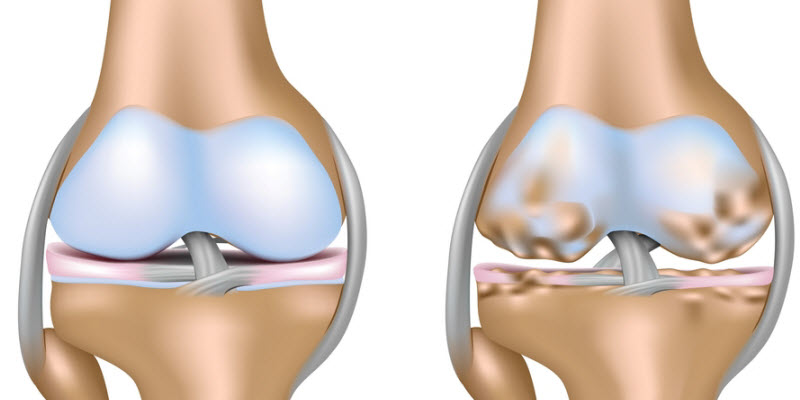

La osteoartritis se produce cuando la amortiguación natural entre articulaciones en el cuerpo se desgasta, lo que permite que los huesos se rocen. Con un estimado de 27 millones de personas de sucumbir a la osteoartritis, hay un interés significativo en la búsqueda de formas para prevenir o tratar la condición.

En comparación con los voluntarios con niveles saludables, los participantes con niveles bajos de vitamina D tenían más del doble el riesgo de contraer la enfermedad. Las personas que tenían tanto altas concentraciones de PTH, vitamina D baja tenían tres veces más probabilidades de empeorar durante el estudio que aquellos con niveles normales de ambos.